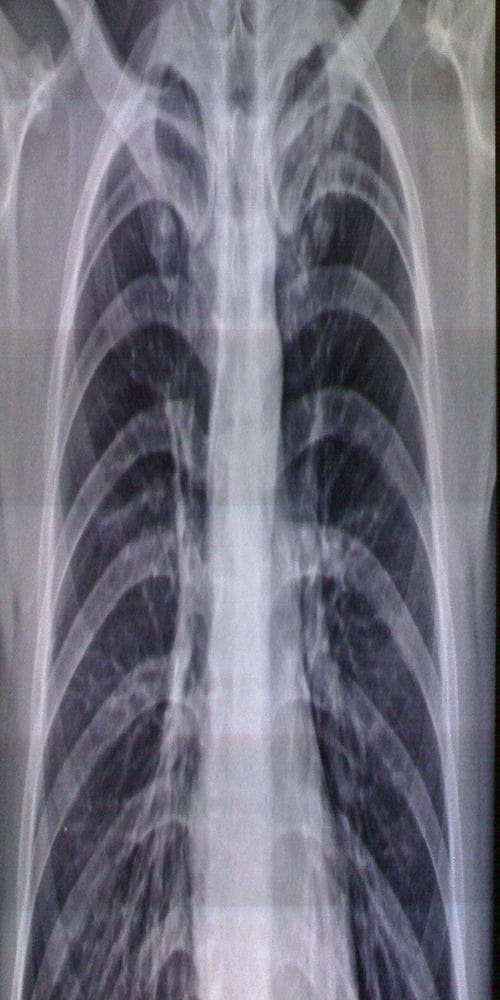

弥漫性阻塞性肺气肿:①胸廓呈桶状,前后径增宽,肋走行变平,肋间隙增宽,横膈较低平,膈活动度减弱。②两肺野透明度见增加,呼、吸时其改变不大,可见单或多发肺大,肺纹理可见稀疏变细,中外带纹理可消失,肺门处肺纹理可增粗,伴有肺间质纤维化时,肺纹理不减少而增强,并可呈网状或蜂窝状。③心景居中而狭长呈垂滴状。